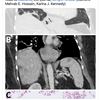

เธอยังมีอาการซึมเศร้าและหลงลืม ก่อนที่ศัลยแพทย์ระบบประสาทที่โรงพยาบาลแคนเบอร์ราจะพบความผิดปกติในสมองกลีบหน้าด้านขวาของเธอระหว่างการสแกนเอ็มอาร์ไอ ในปี 2022

เมื่อแพทย์ทำการผ่าตัดสมองเพื่อตรวจสอบ พวกเขาพบพยาธิตัวกลม โอฟิดาสคาริส โรเบิร์ตซิ (Ophidascaris robertsi) ขนาด 8 ซม. ซึ่งนักวิทยาศาสตร์เชื่อว่าเป็นครั้งแรกที่พบพยาธิชนิดนี้ในมนุษย์